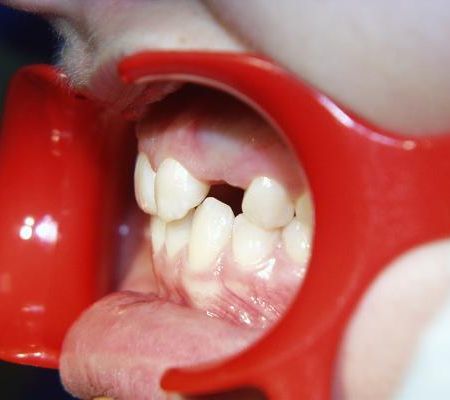

Vor der Behandlung

Ein oberer Eckzahn war zu einem früheren Zeitpunkt vom Hauszahnarzt verbreitert worden, um eine besonders auffallende Lücke zu schließen. Die Situation war aber wegen der Seitenungleichheit, der atypischen Zahnformen und der noch vorhandenen Lücken immer noch unbefriedigend.